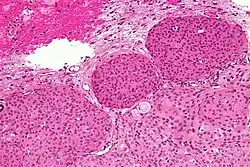

Meningioma meningotelial

Se caracteriza por su microarquitectura lobular y apariencia epiteliode. La neoplasia está poblada de células que tienen núcleos, redondos u ovales, de cromatina delicada y nucleolos poco llamativos. Los citoplasmas son eosinófilos, claros, y el borde citoplasmático indistinguible, de ahí su designación alternativa como meningioma sincitial. Es común, al igual que en otros subtipos, que las células tumorales se agrupen en apretadas espirales. También son frecuentes los núcleos claros, las pseudoinclusiones nucleares pálidas, resultantes de invaginaciones intranucleares del citoplasma, y la presencia de calcoesférulas laminadas, denominadas cuerpos de psammoma. Los hallazgos descritos son considerados como clásicos de los meningiomas y, aunque ninguno de ellos es patognomónico, su demostración tiene un considerable peso diagnóstico.